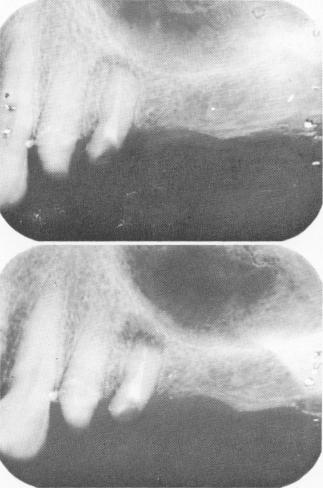

Fig. 15-60. A, The framework was fitted into position and radiographed in order to determine where to drill the holes in the template to accommodate the pin implants. B, The framework was cemented into position over the two anterior bicuspid preparations after the holes were made through the template outside the mouth.

A

B

4 Xray of framework over template to determine pin implant position